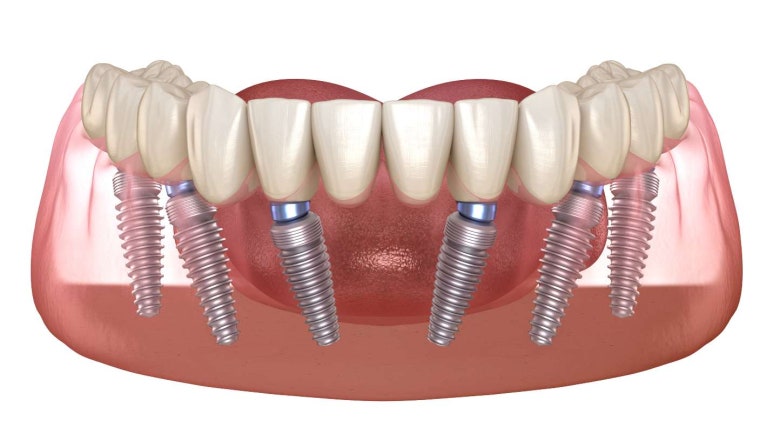

아래턱 전체 치아를 회복하기 위해 모든 자리에 임플란트를 심을 필요는 없습니다.

이번 사례에서는 '올온식스' 공법을 적용했습니다.

• 핵심 원리: 가장 튼튼한 뼈 위치에 6개의 임플란트 기둥을 전략적으로 식립합니다.

• 브릿지 결합: 심어진 6개의 기둥 위에 하나의 일체형 전체 보철물을 연결하여 전체 치열을 회복합니다.

• 장점: 식립 개수가 적어 비용 부담은 줄이면서도, 저작력(씹는 힘)은 자연치아의 80% 이상까지 끌어올릴 수 있습니다.